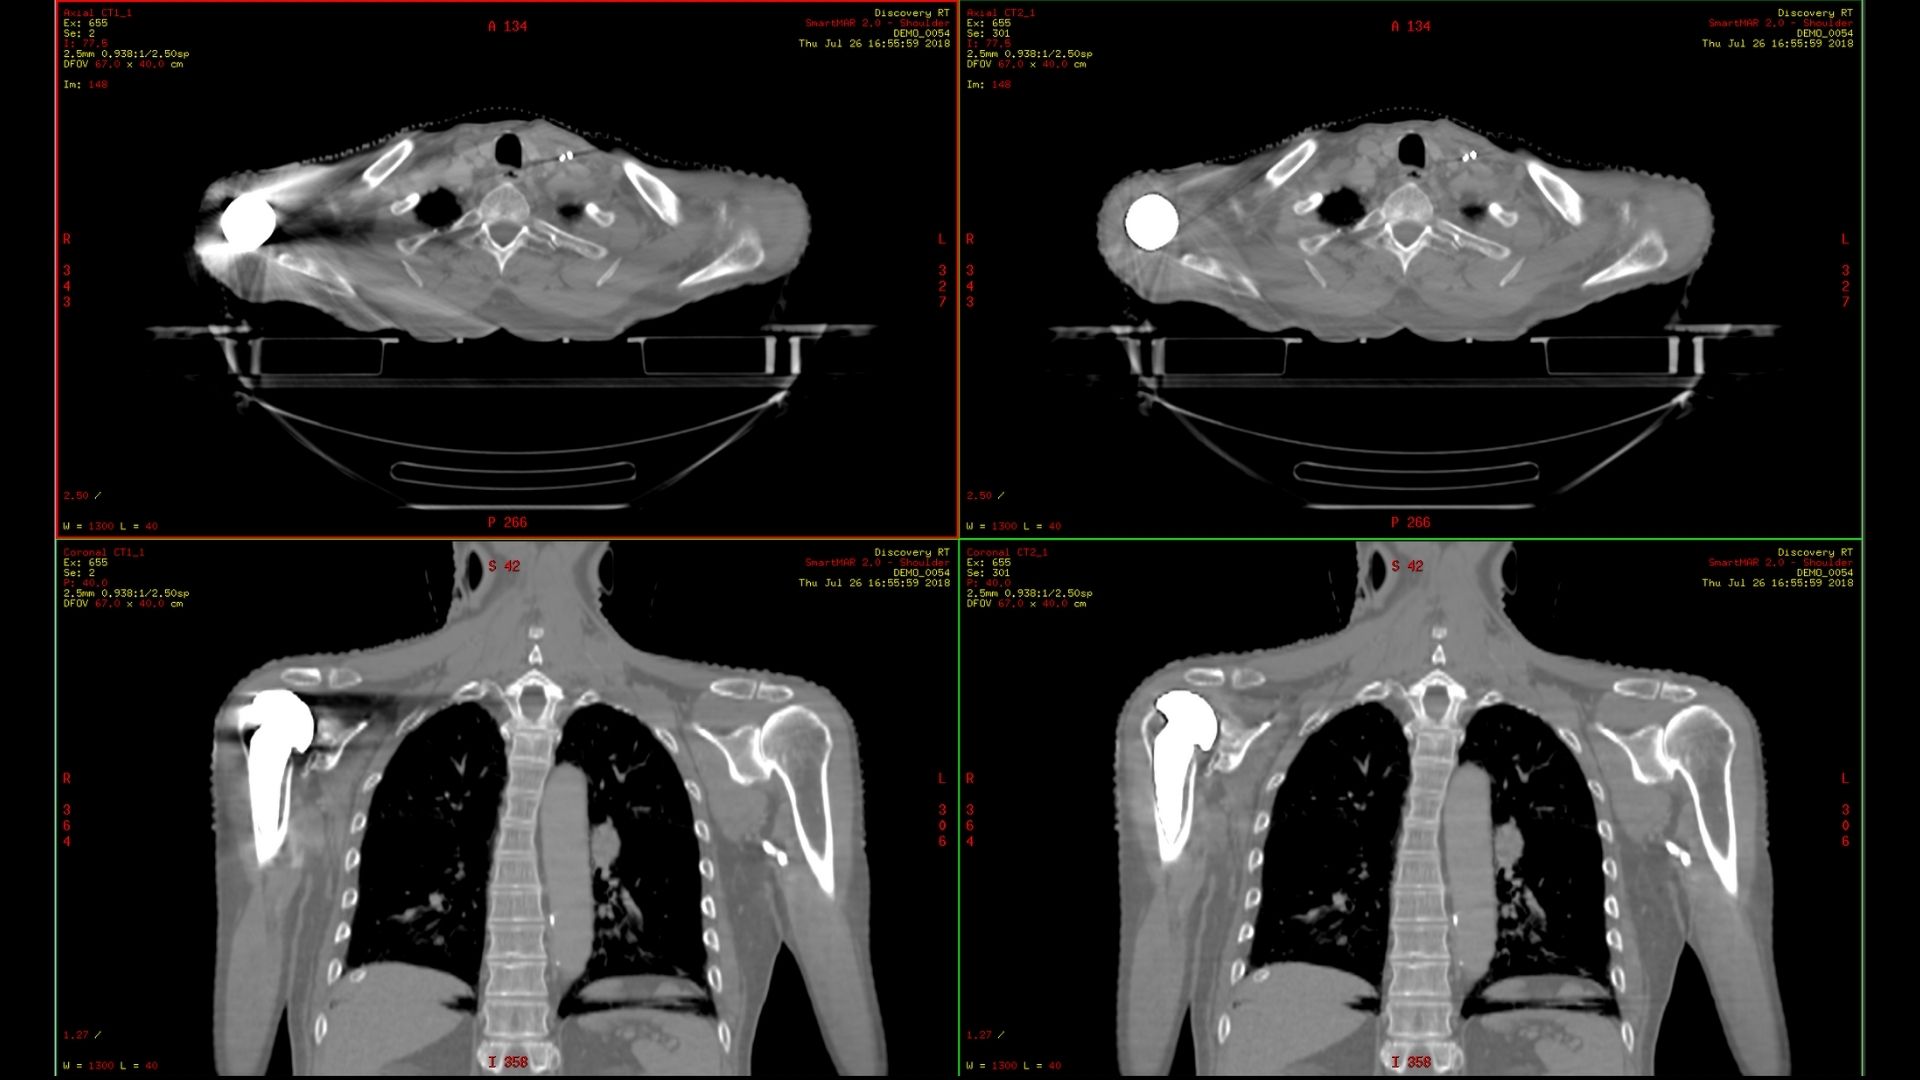

Замена правого плеча с коррекцией SmartMAR 2.0 и без нее